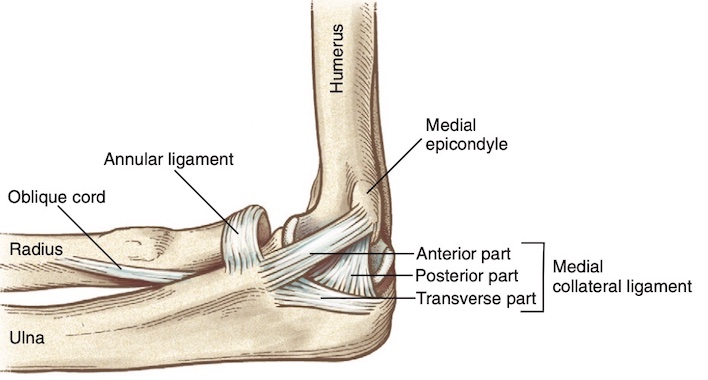

- Dây chằng bên trong (Hình 1), hay dây chằng bên trụ, bao gồm ba phần: đoạn trước, sau và ngang. Bó trước là thành phần mạnh nhất và nổi rõ nhất, trong khi bó sau là sự dày lên của phần sau của bao khớp và cung cấp sự ổn định ở góc gập 90 độ.